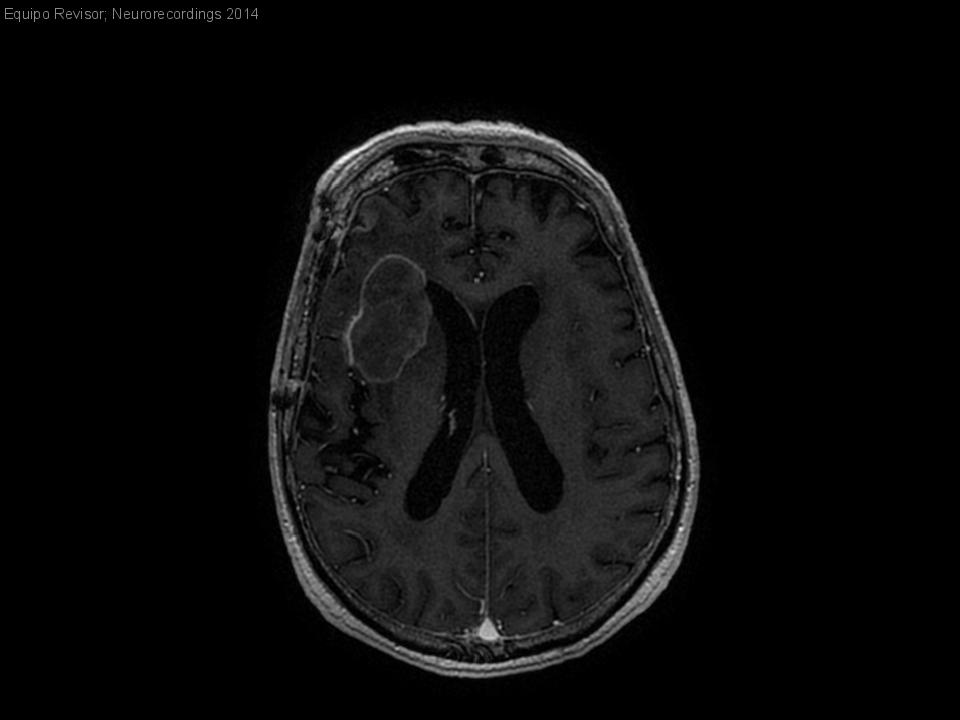

¿Absceso o tumor?

Hombre | 65 años

Diagnóstico final: Metástasis de carcinoma pulmonar de célula grande